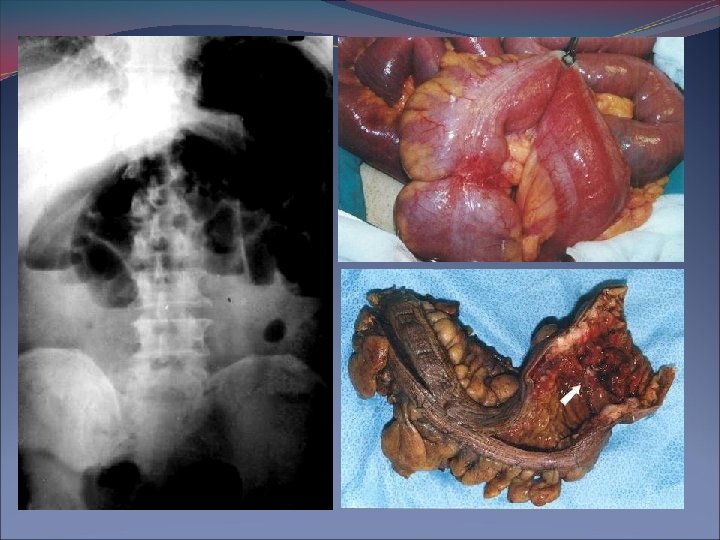

Px. Con Obs. Mecánica de ID: NO Presencia de gas en colon. Rx. Posición de pie o decúbito lateral: Niveles múltiples de gas y líquido, con distensión intestinal en forma de U invertida Rx. Abdomen con Obs. Colon más: § Válvula ileocecal competente: Distensión del colon § Válvula ileocecal incompetente: Distensión de ID y Colon.

Signos de huellas digitales, pérdida del patrón mucoso, gas dentro de la pared intestinal o ramas intrahepáticas de la vena porta estrangulación de la obstrucción. Placa en bipedestación o en decúbito lateral, aire libre intraperitoneal perforación intestinal. Íleo paralítico distensión gaseosa de distribución uniforme en estómago, ID. y colon.

Imagenología Enema baritado: Bario se detiene en la obstrucción toma forma de huso (deformación en pico de pájaro) no en paciente con sospecha de gangrena

VÓLVULO: Segmento de intestino delgado con una zona de torsión.

Ecografía: Uso controvertido por los artefactos que ocasiona el gas intestinal. No obstante, permite detectar asas edematizadas, patología biliar (íleo biliar), presencia de líquido libre peritoneal, abscesos así como patología renal causa de íleo reflejo. Enema opaco: Debemos solicitarlo ante la sospecha de una tumoración obstructiva o estenosante para diagnosticarla y comprobar el grado de obstrucción. En caso de vólvulo intestinal puede ser diagnóstico y terapéutico.

Colonoscopia: Menos útil por la difícil preparación colónica del paciente, pudiendo ser terapéutica en casos de vólvulos (sería el tratamiento de urgencia, y si fracasa la desvolvulación o se sospecha gangrena o perforación estará indicada la cirugía urgente) o diagnóstica (neoplasias). TAC y RMN: Valoración de patologías no diagnosticadas por los anteriores medios, pues detectan dilatación diferenciada de asas, participación o complicación peritoneal y retroperitoneal.